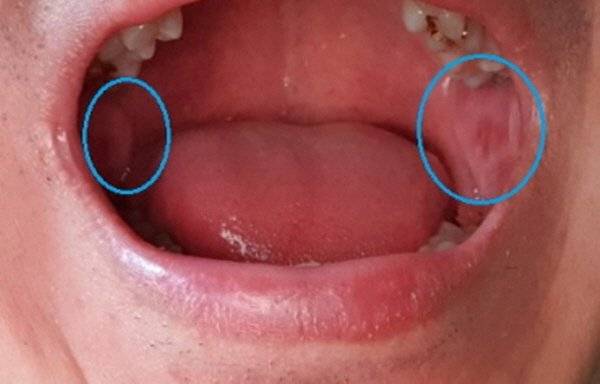

이번에는 한 손에 이렇게 거울을 들고, 눈 상태를 한번 체크해 볼까요? 먼저 눈꺼풀 안쪽 색깔을 확인해 주세요.

눈꺼풀을 아래로 살짝 당겼을 때, 안쪽 점막에 이렇게 예쁜 분홍빛이 돌고 있으면 정상! 이상하게 하얗고 창백해 보인다면 혈액 내 헤모글로빈 수치가 낮아 산소 공급이 원활하지 않다는 뜻으로, 빈혈이나 철분 결핍을 의심해 볼 수 있다고 합니다.

눈꺼풀 안쪽이 유난히 붉다면 피로감이 심하다는 신호이니 충분한 휴식을 취해주셔야 할 타이밍이구요.

그런데 혹시 이 안쪽에 얼룩덜룩, 반점 같은 것들이 보이시는 분 계신가요? 이런 경우에는 각별한 주의가 필요합니다. 혈액 내에 작은 혈전이 생겨서 떠돌아다니다가 가느다란 모세혈관(실핏줄)에 와서 걸리는 것일 수도 있거든요.

심장이나 목에 있는 경동맥에 동맥 경화나 염증이 생긴 영향일 수도 있고, 심해지면 '뇌경색'이라고 하는 중풍 발생의 원인이 되기도 하니 이런 반점이 보이신다면 즉시 병원에 방문하셔서 자세한 진단을 받아보셔야겠죠?